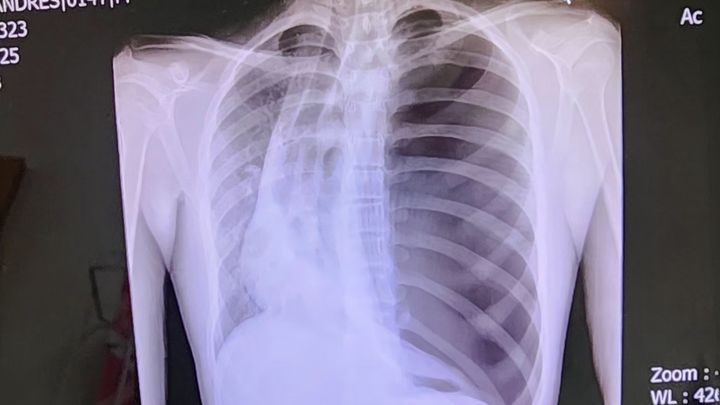

Hello, my name is Andy. I recently was hospitalized with a collapsed lung. I'm 14, a freshman at HISD. Anything will help with helping my family pay for any medical expenses not covered by insurance.

My doctor is planning a surgery to correct what's causing my lung to collapse this coming week. Thank you!